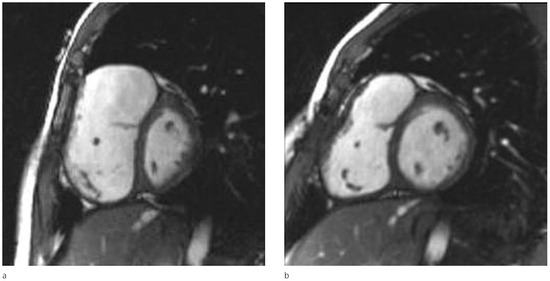

The Right Ventricle in Tetralogy of Fallot

by Emanuela Valsangiacomo Büchel and Dominik Stambach

Cardiovasc. Med. 2009, 12(9), 234; https://doi.org/10.4414/cvm.2009.01445 - 18 Sep 2009

Cited by 2 | Viewed by 291

Surgical repair of tetralogy of Fallot (TOF) may be followed by various conditions and residual findings, early postoperatively or late during follow-up. Most of these conditions affect the right ventricular outflow tract and the pulmonary arteries and thus, indirectly, the right ventricle.

This paper discusses the role of the right ventricle during the natural history of repaired TOF. The different imaging methods used to assess the function of the right ventricle in relation to this congenital heart disease are highlighted. Particular attention is focused on the volume overloaded right ventricle, as this condition is nowadays a subject of intense discussion, particularly regarding the appropriate timing for pulmonary valve replacement. The most recent literature on this topic is briefly reviewed. In summary, preservation of right ventricular function and prevention of right ventricular arrhythmias are crucial for these patients’ survival and outcome. Full article

Figure 1